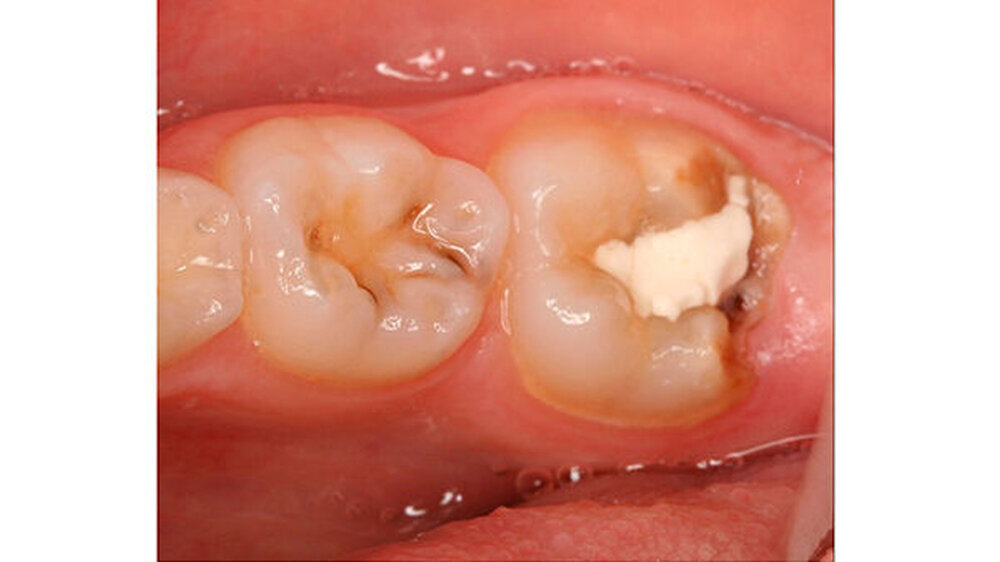

Wie im Fall zur Füllungstherapie ausführlich beschrieben, ist der Haftverbund der derzeit verfügbaren Materialien aufgrund des hypomineralisierten Schmelzes in der Regel nicht zufriedenstellend und oft von einem frühzeitigen Füllungsverlust und/oder einem weiteren Einbruch in den an die Restauration angrenzenden Bereichen begleitet (Abbildungen 9 und 10).

Für kleine und mittelgroße Defekte sind Komposite sehr gut geeignet. Wenig kann zu der Verwendung eines geeigneten Adhäsivsystems gesagt werden, aus einer knapp zehn Jahre alten Untersuchung geht hervor, dass self-etch Systeme möglicherweise den total-etch Systemen überlegen sein können, weil es hier nicht mehr zu Interferenzen nach dem Abspülen kommt. Die größte Schwierigkeit besteht hierbei aber, dass für eine akzeptable Haltbarkeit dieser Restaurationen gefordert wird, die Kavitätenränder in gesunden Schmelz zu legen. Aufgrund des Umfanges der Läsionen sind die Voraussetzungen für diese Maßnahme nur selten erfüllt (vgl.Fallbeispiel auf zm-online). (Abbildung 12).